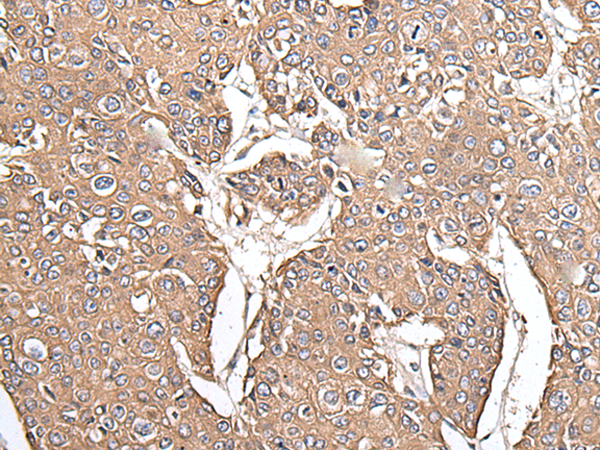

IHC positive control: |

Human prostate cancer and human lung cancer |

IHC Recommend dilution: |

40-200 |